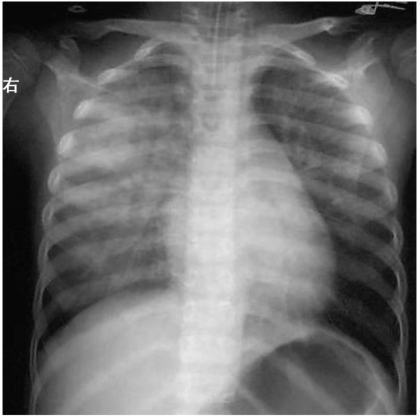

重症及危重症患儿并发神经源性肺水肿时,两肺野透亮度减低,磨玻璃样改变,局限或广泛分布的斑片状、大片状阴影,进展迅速(图 1)。

图1神经源性肺水肿

胸部X线检查提示两肺野透亮度减低,广泛分布的大片状阴影